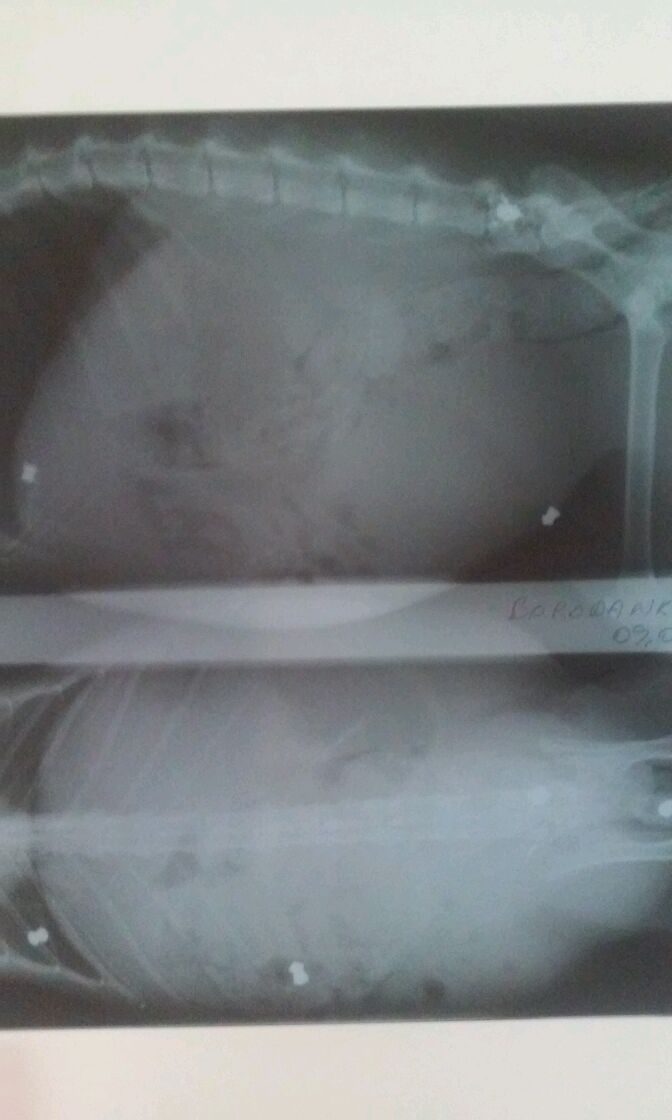

Sellega ei lõppenud kassi piinad. Ka järgneval aastal sai kassike tõsiselt vigastada. Röntgen näitas kolme kuuli loomakese kehas, millest üks kuul purustas selgroo. Vigastus viis alumise kehaosa halvatuseni. Kass ei saanud normaalselt kõndida, saba ei liikunud ja ka pissimine oli raske. Kolm aastat peale vigastust kahjuks kass suri, sest ta organism ei allunud ravile.